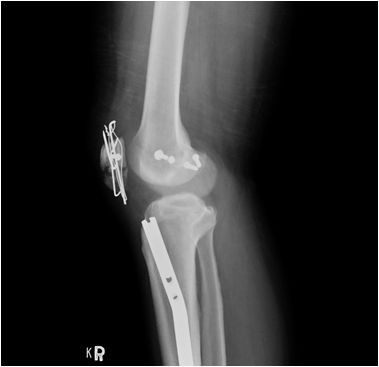

圖:手術治療前後的膝蓋與小腿。

圖:為了保住洪國程的右腿,鄺世通醫師用上鋼板、鋼索、補丁等各種可以的治療方式。

而當時的主治醫師就是個性直率低調,被同事與後進同仁暱稱為鄺爺的骨科鄺世通醫師,這個在鄺醫師口中的小骨折,其實是包含髖關節、大腿股骨、膝蓋髕骨、與小腿脛骨等多處粉碎性骨折的複雜個案,不論是X光檢查,還是電腦斷層檢查,都能看見因為強力撞擊穿出髖關節的股骨,還有粉碎的髕骨,歷經數個小時的開刀,才救回洪國程先生的性命與右腿。

後來洪國程才知道,當時鄺醫師可以說是像是在拚一個摔破的瓷碗,一塊一塊地把他的骨頭拼回去,然後再細心的照顧他的傷口,才讓他免去截肢的痛苦,洪國程回想起來,心有餘悸的說:「當時我才35歲,正當年輕而且小孩還小,真的無法想像下半輩子要坐輪椅的生活。」